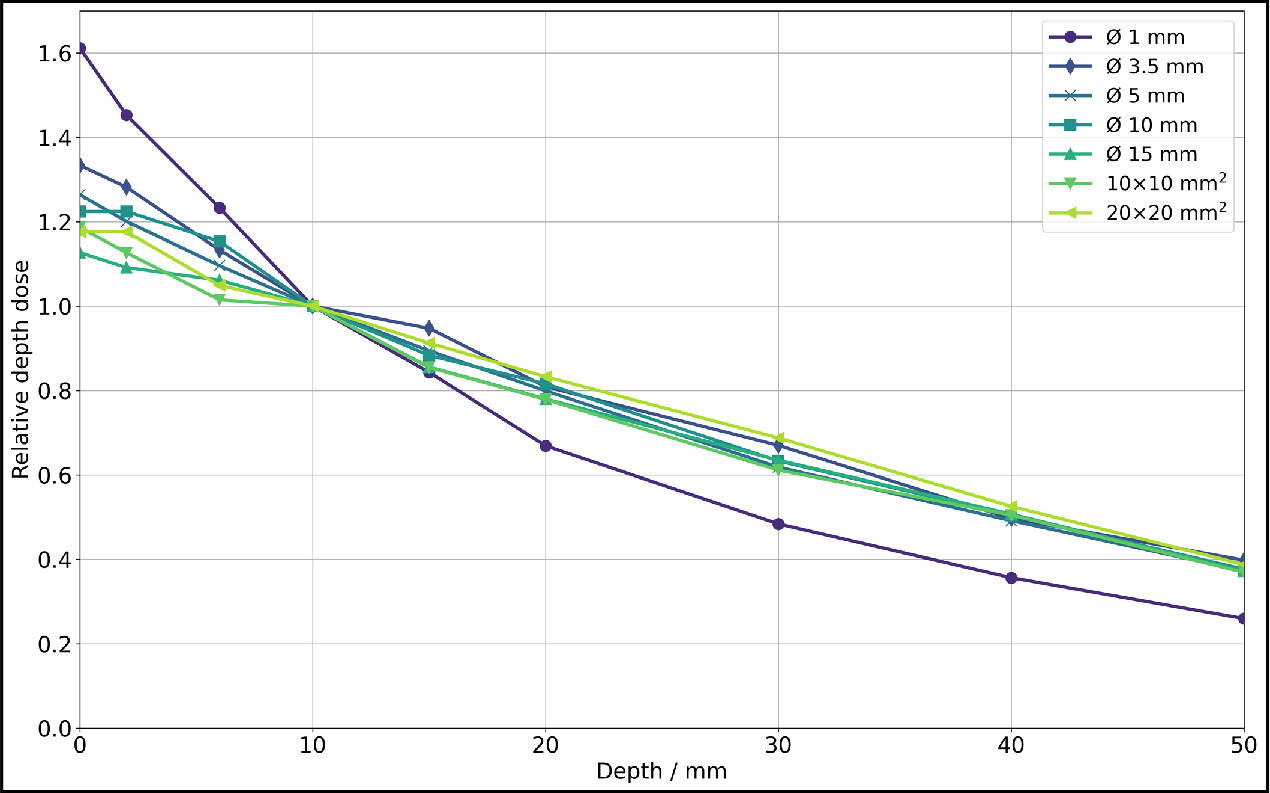

The dose rates for all investigated collimators can be found in table 1. The dose rate was calculated from the difference between the 80 s and 20 s exposed films, each including all dose values from a 9 × 9 px2 (0.76 × 0.76 mm2) field centered around the center of mass. It is evident that for larger collimators, the available dose rate is higher. Based on the dose rate values, relative depth dose profiles were determined and illustrated in figure 6, with normalization to a depth of 10 mm due to the greater fluctuation of surface dose values.

Figure 6. Relative depth dose for photon irradiation for all collimators at 200 kV x-rays (0.5 mm Cu filter, HVL: 1.03 mm Cu) of SmART+ IB, measured with EBT3 films (relative measurement uncertainties <7%). Normalization to a depth z = 10 mm was performed due to the greater fluctuation of surface dose values.